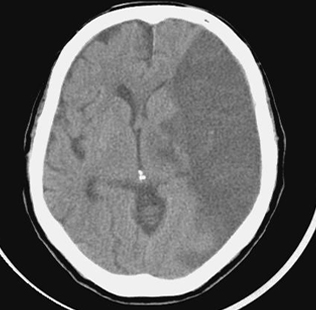

뇌경색 초기증상에 대하므로 살펴볼게요니다. 뇌에도 혈관이 있어서 피가 흐르고 있어요. 뇌에 있는 혈관이 막혀서 뇌의 일부가 손상되는 것을 뇌경색이라고 말해요. 뇌혈관이 막혀 뇌가 손상되면 장애가 발생할수 도 있으므로 뇌 연관 질환은 각별한 주의가 필요해요.

뇌에 제공되는 혈액량이 줄어들게면 뇌가 수습해야 되는 역할들을 제대로 실행해 낼 수 없게 돼요. 뇌혈류가 연속적으로 감소되면 뇌조직에 괴사가 시작되고 괴사된 뇌조직이 회복 불가능한 상태가 되면 뇌경색이라고 진단을합니다. 그러므로 뇌경색 초기증상을 알아두고 방지해억제해하시는게 중요해요.

뇌경색은 병에 걸려 후 얼마나 빨리 치료를 착수하는지에 따라 병의 증세가 결심되기도 합니다. 증상이 발생하면 아주많이 빨리 병원을 가서 초급성기 치료를 받아야합니다. 급성기 치료 후에는 이유가 되는 것에 따라 재발 방지를 위한 치료를 하게 되며 후유증에 대한 재활치료도 가능한 한 빨리 실행하는는게게 좋바람직해요. 증상이 처음 나타난 후 4~5시간이 경과하지 않으신다면 주사 제제를 통한 혈전용해술을 시도해 볼 수 있어요. 그리고 24시간이 경과하지 않았고 대뇌혈관이 막힌 것을 확인했으면 막힌 혈관에 대하여서 스텐트 투여술과 같은 기계적 재개통술을 시도할 수 있습니다.